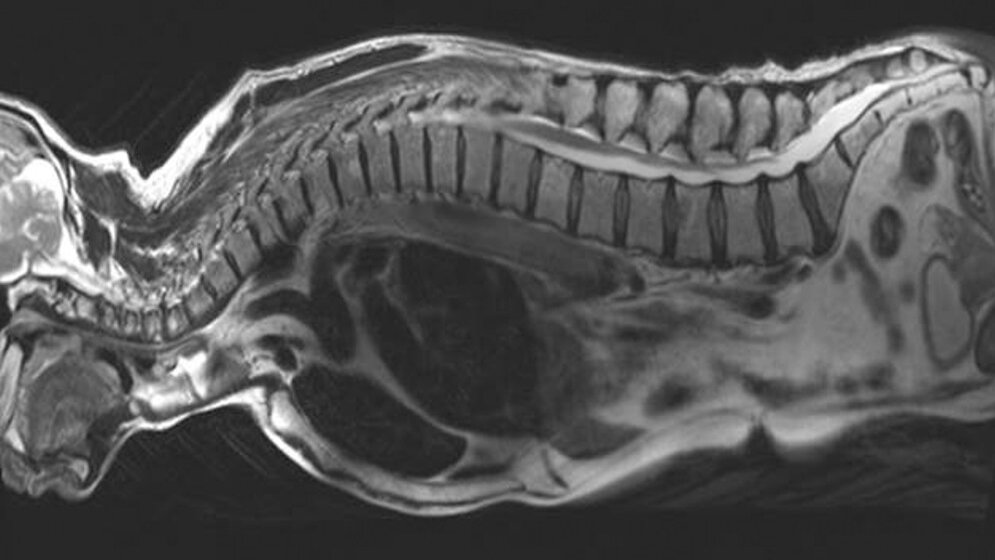

Bisher werden bei den bildgeführten Bestrahlungstechniken unmittelbar vor dem Start der Bestrahlung die Lagerung des Patienten und damit auch die aktuelle Position des Tumors über Röntgenbildsysteme wie die Kegelstrahl-Computertomographie (CT) kontrolliert. Eine MRT wäre der CT allerdings überlegen: Mittels MRT lassen sich die Unterschiede zwischen Tumor und gesundem Gewebe, der sogenannte Weichteilkontrast, und damit die Tumorgrenzen besser abbilden. Zudem liefert sie zusätzliche aktuelle Informationen aus dem Inneren des Tumors, z.B. ob dieser gut oder schlecht durchblutet ist, oder welche Bereiche eine hohe Stoffwechselaktivität aufweisen. Forschungsergebnisse haben gezeigt, dass sogenannte hypoxische Tumorbereiche mit geringer Sauerstoffversorgung weniger empfindlich gegenüber Strahlung sind und daher eine höhere Dosis benötigen. Die Informationen dieser „biologischen Bildgebung“ erlauben nun möglicherweise, die benötigte Strahlendosis für die einzelnen Tumorareale besser anzupassen. Nicht zuletzt kommt die MRT ohne zusätzliche Strahlenbelastung des Patienten aus und kann daher problemlos mehrmals wiederholt werden.

Tumoren verändern im Laufe der oft mehrere Wochen dauernden Therapie ihre Größe. Auch während einer Therapiesitzung kann die Lage des Tumors sich verändern, z.B. durch Atembewegung. „Die Kombination von Strahlentherapie mit MRT ermöglicht einen enormen Entwicklungssprung gegenüber den CT-gesteuerten Verfahren“, ist Debus überzeugt. „Die hervorragende Bildqualität ohne Strahlenbelastung ermöglicht prinzipiell, den Tumor während der Therapie in kurzen Intervallen zu beobachten und bei Bewegungen und Veränderungen die Strahlung direkt anzupassen.“